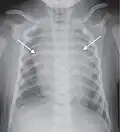

Chest film showing increased opacity in both lungs, indicative of pneumonia -